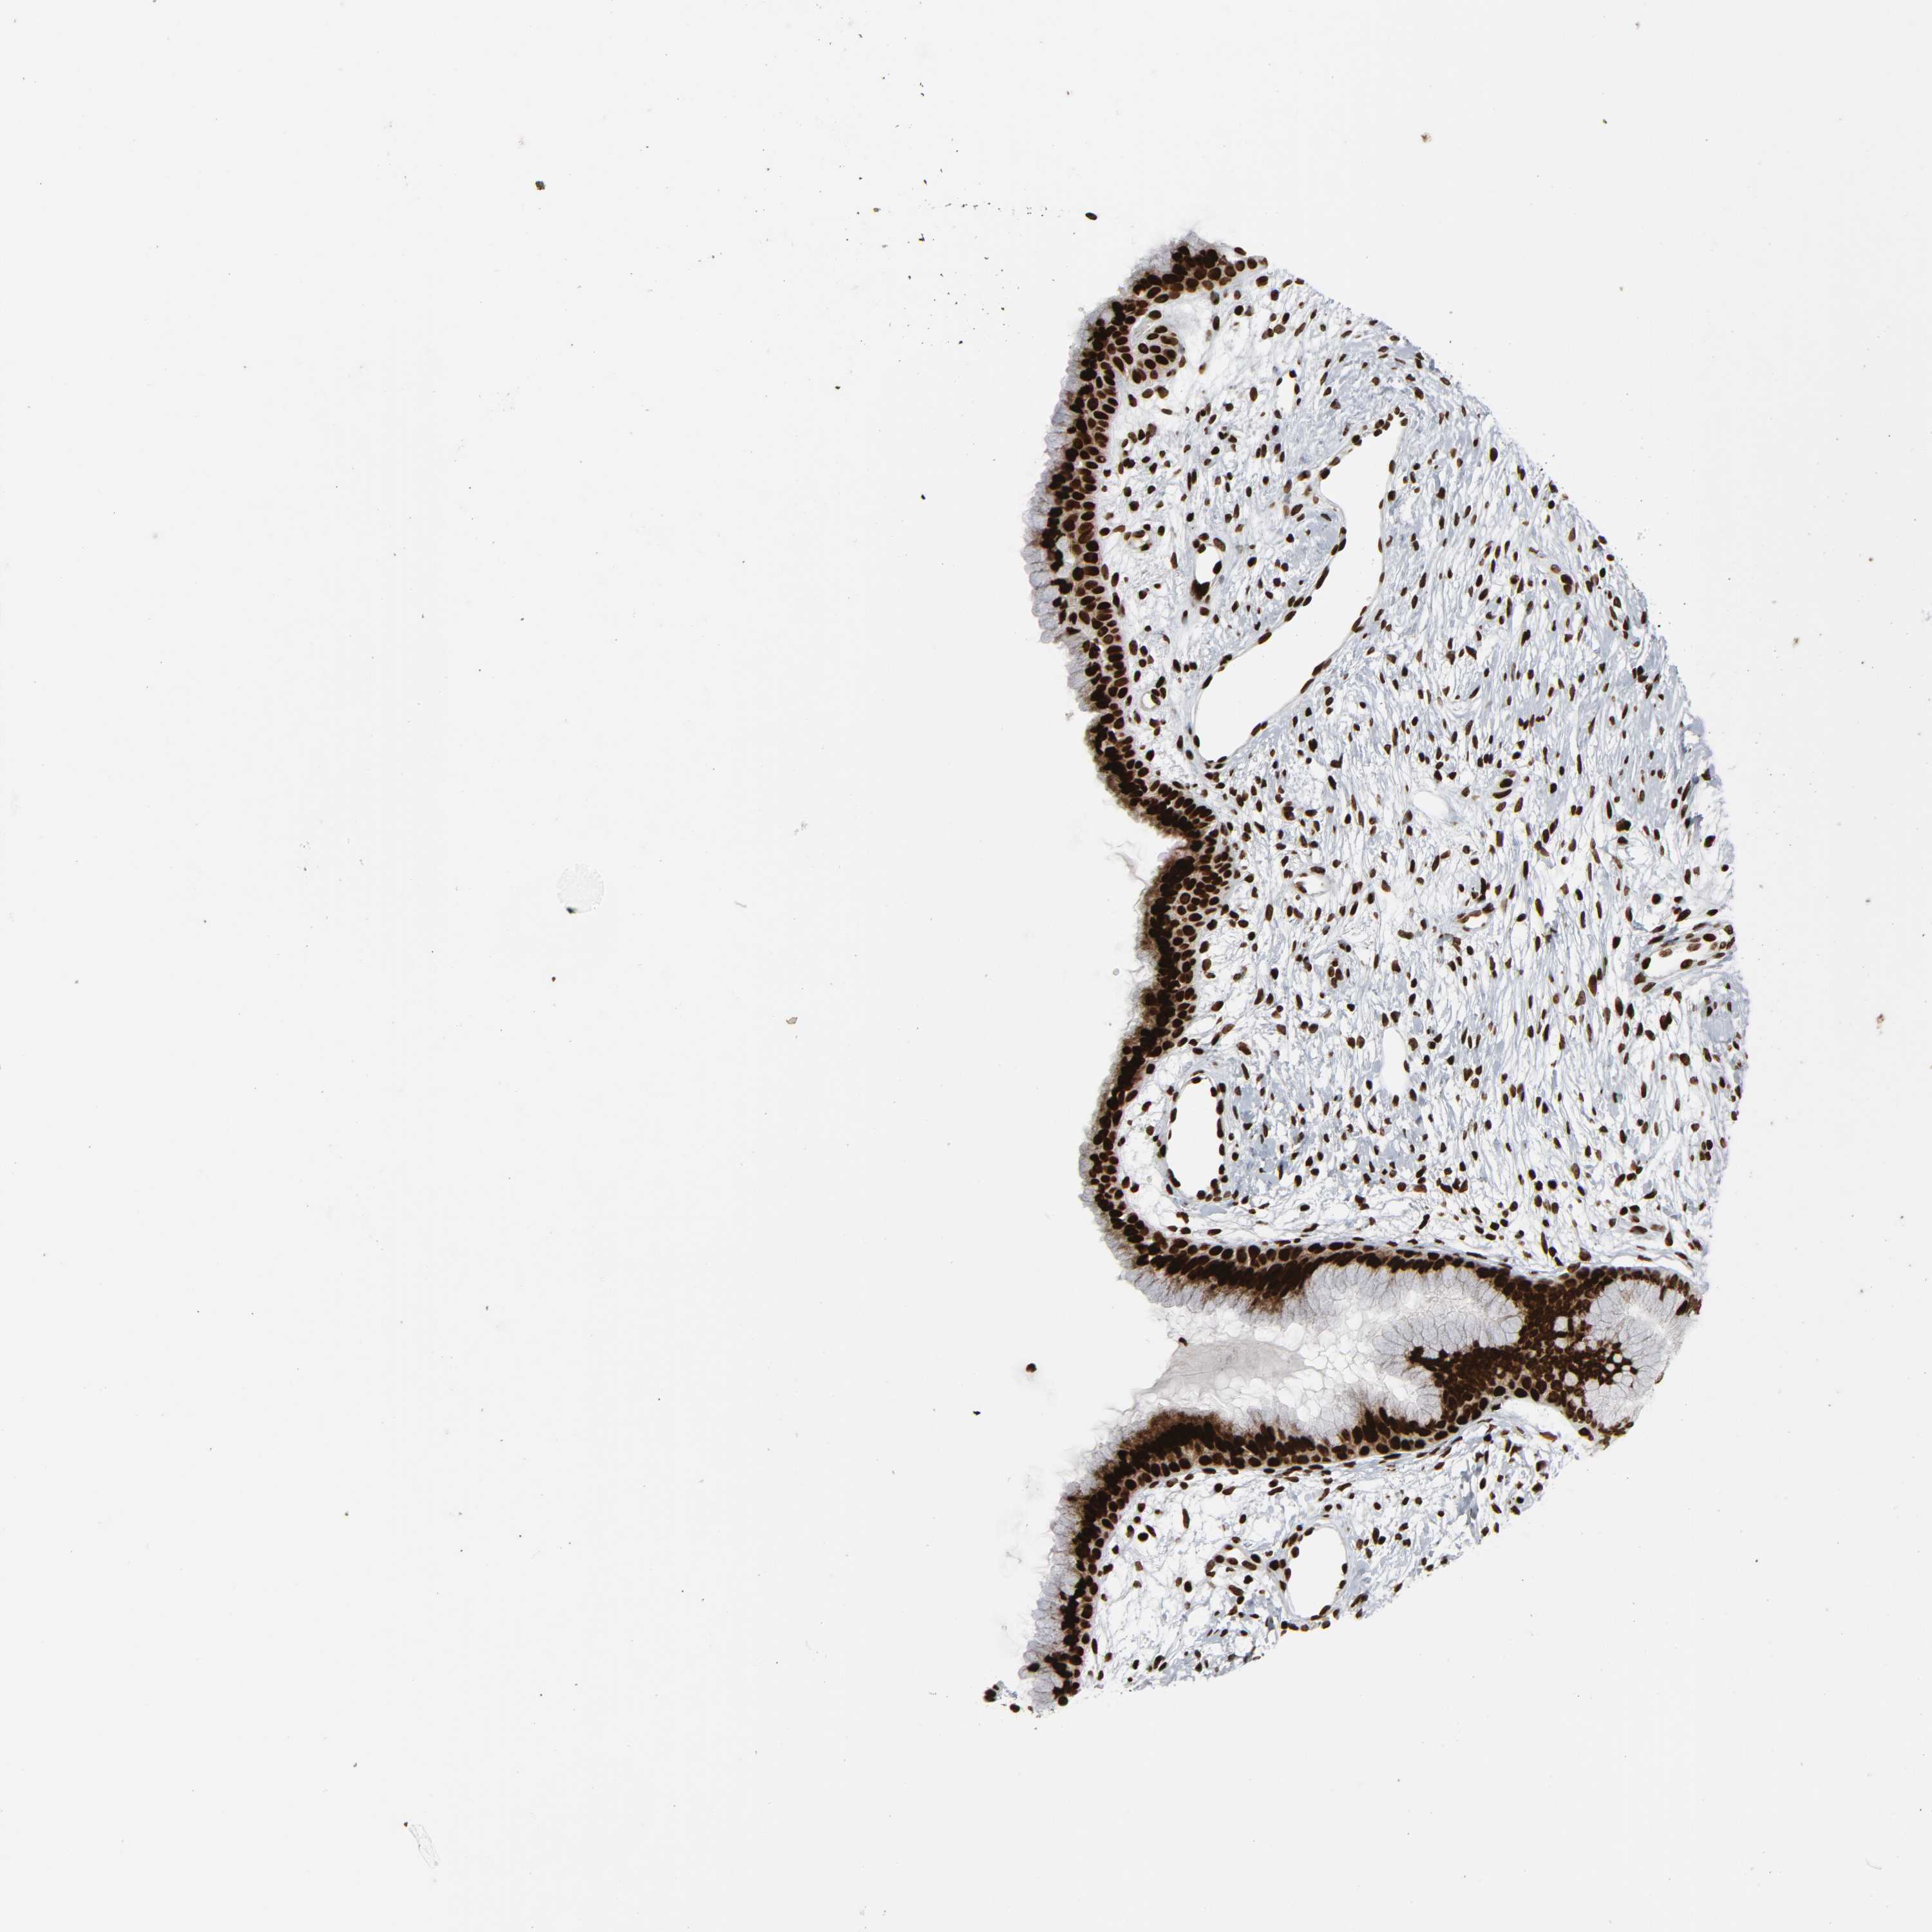

CERVIX - Antibody stainingi

Antibody staining in the annotated cell types in the current human tissue is reported as not detected, low, medium, or high, based on conventional immunohistochemistry profiling in selected tissues. This score is based on the combination of the staining intensity and fraction of stained cells.

Each image is clickable and will lead to virtual microscopy that enables deeper exploration of all samples and also displays staining intensity scores, fraction scores and subcellular localization as well as patient and tissue information for each sample.

Antibody CAB004565Antibody CAB005352

Glandular cells HighMedium

Squamous epithelial cells MediumHigh